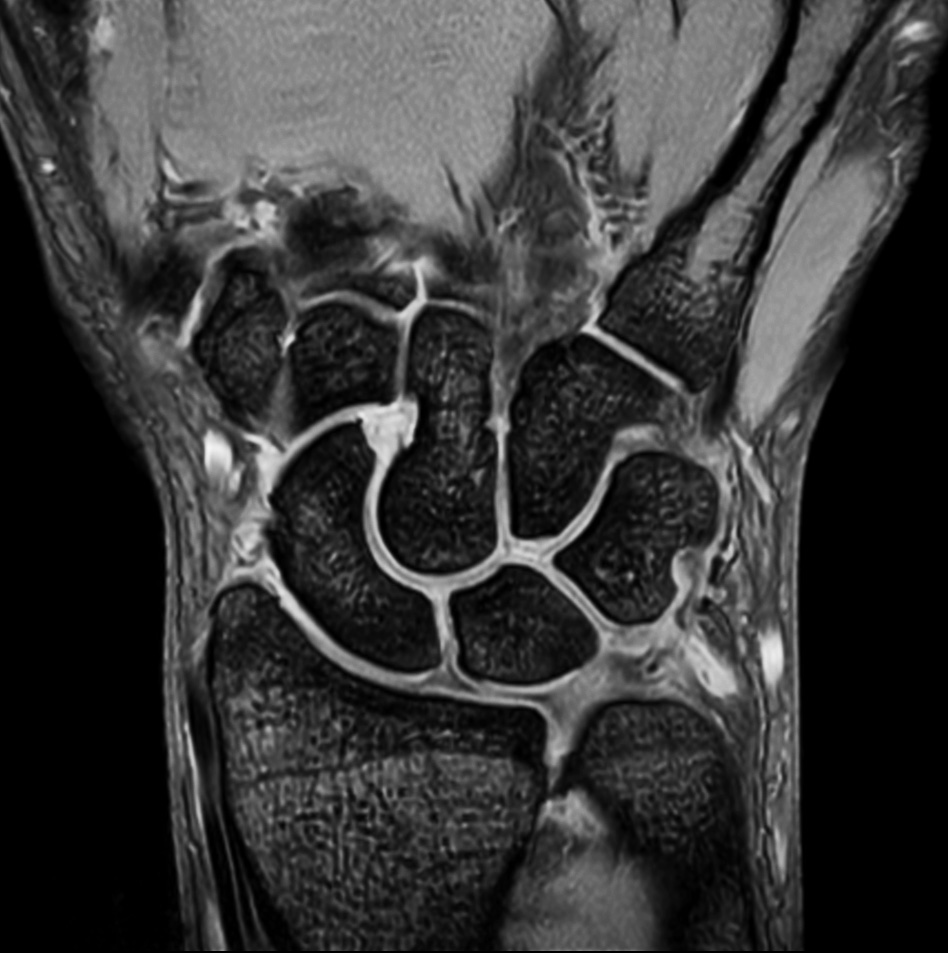

Comprehensive wrist imaging